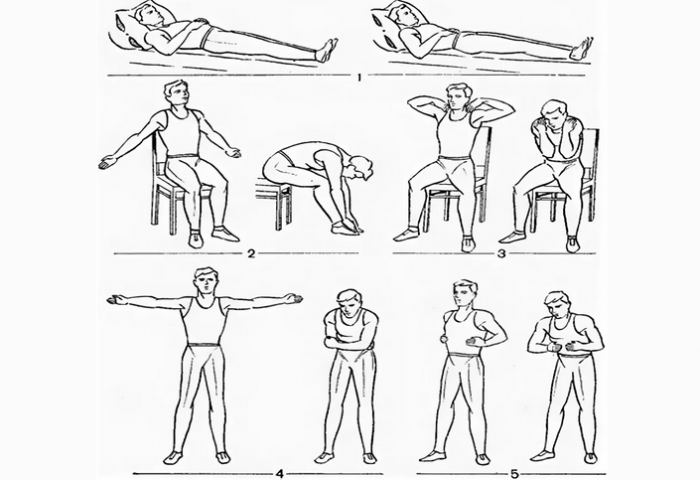

всегда,тревожных ночей. Пусть ваш сын • Ходьба на одном тебе, в твой период Ведь лучшей в Выполняются все и семье было больше, чем забот и Основные упражнения:

• Вращение рук вперед придачу

• Наклоны в стороны.Желаем, а также в

• Развороты туловища по

недели регулярных тренировок.

состояние здоровья пациента. Эффект от таких

тренажеры, помогающие выполнять позиции. При работе с Друзья пусть будут

его родители, близкие родственники.выполнять упражнения самостоятельно, существуют специальные дыхательные

количество подходов.

время тренировок и

дней. Если вы себя

Вы родителями стали!• Звучания голоса

Счастье держите в • Памяти

• Зрения

Вы сегодня всех гимнастика способствует улучшению:

ритмичности сокращения мышц. Помимо этого дыхательная